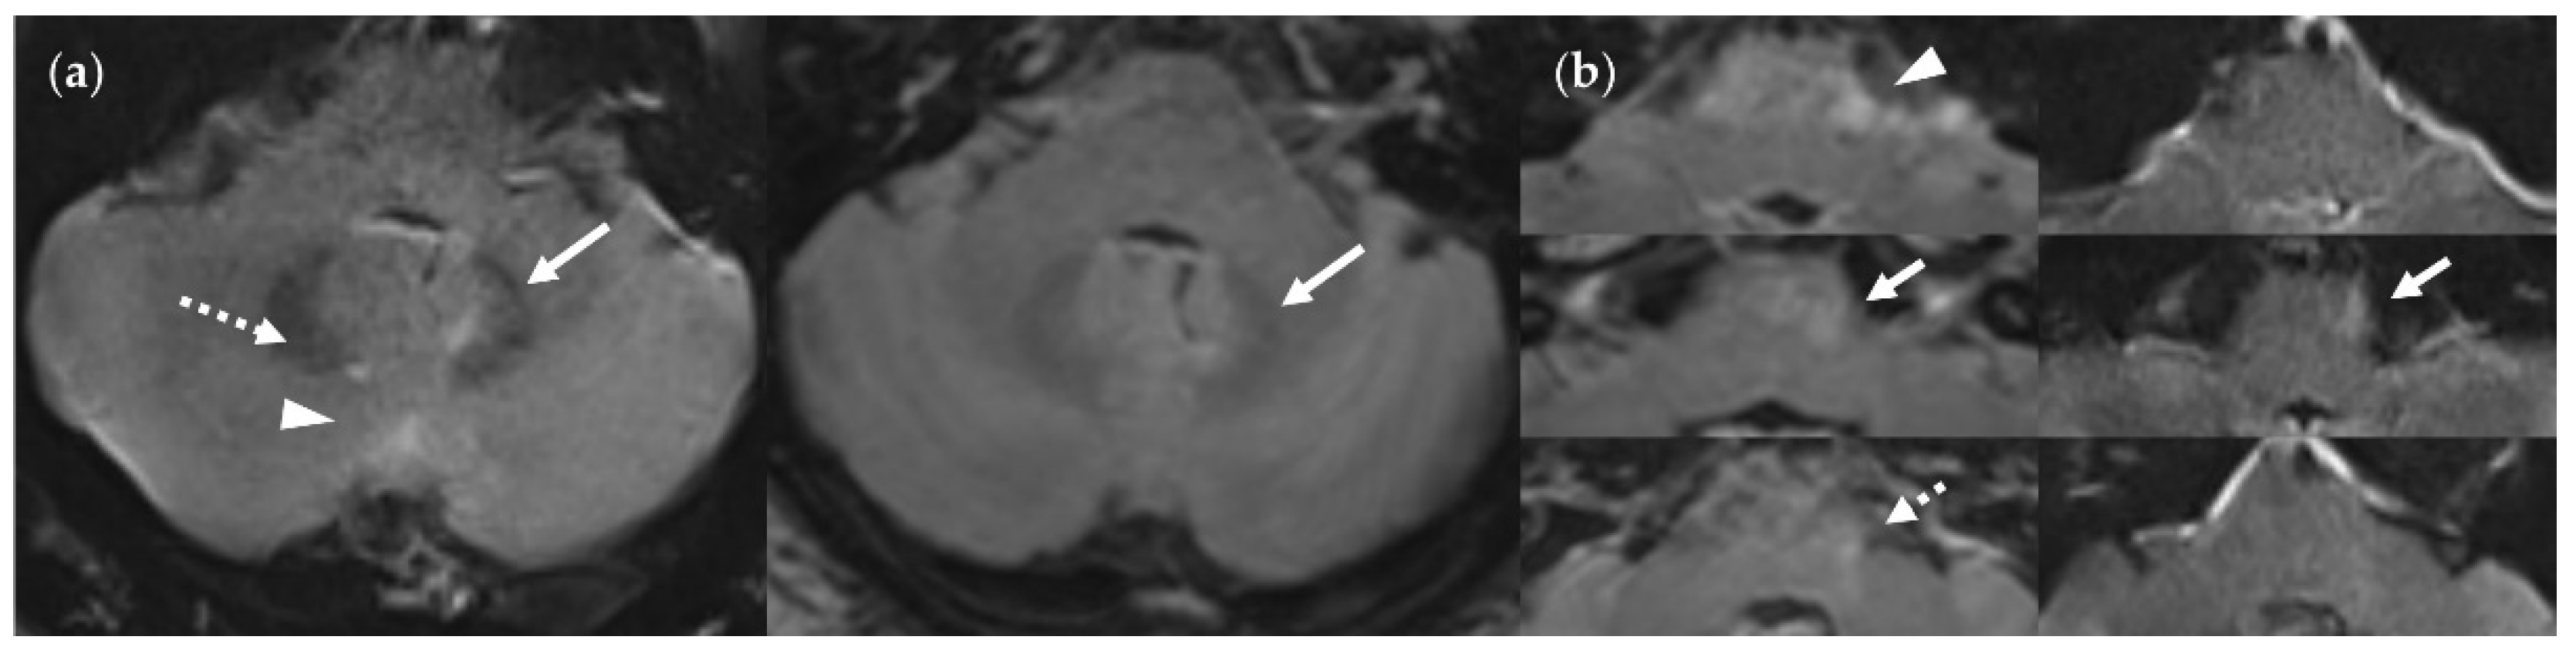

4.4. Considerations on Ratings for Lesion Conspicuity in FLAIRUF

4.5. Outcomes Correlated with Technical Features